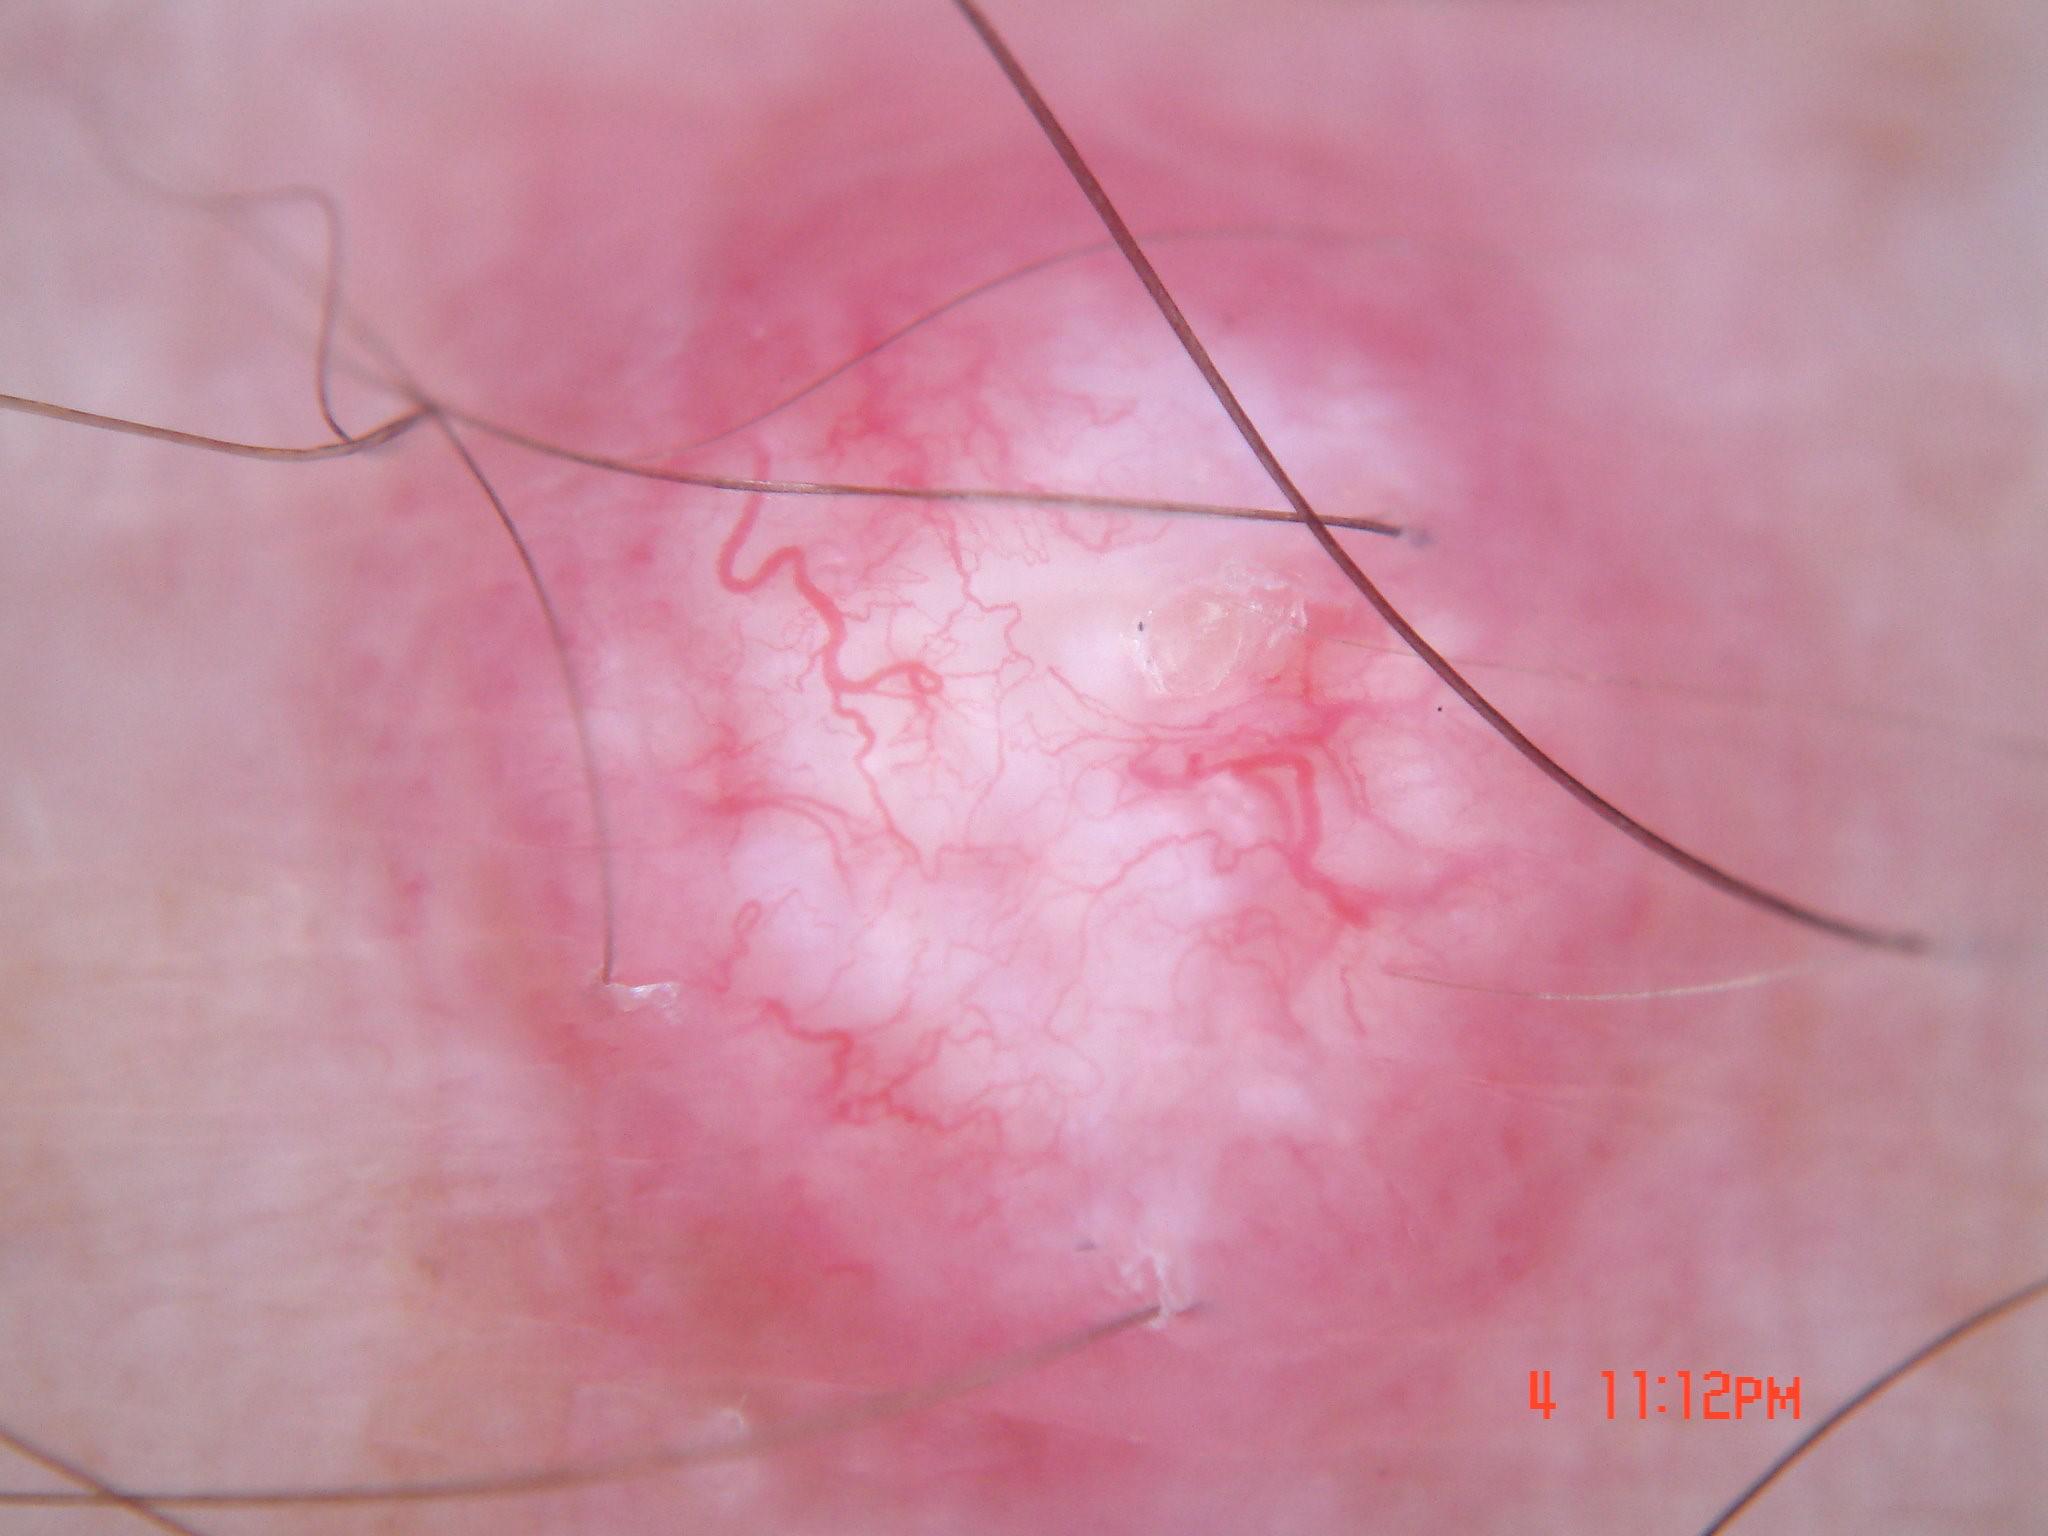

{

"age_approx": 70,

"anatom_site_general": "upper extremity",

"concomitant_biopsy": true,

"dermoscopic_type": "contact non-polarized",

"diagnosis_1": "Malignant",

"diagnosis_2": "Malignant epidermal proliferations",

"diagnosis_3": "Squamous cell carcinoma, Invasive",

"diagnosis_4": "Squamous cell carcinoma, Invasive, Keratoacanthoma-type",

"diagnosis_confirm_type": "histopathology",

"family_hx_mm": false,

"image_type": "dermoscopic",

"melanocytic": false,

"patient_id": "IP_9529293",

"personal_hx_mm": true,

"sex": "male"

}

"dermoscopic_type": "non-contact polarized",